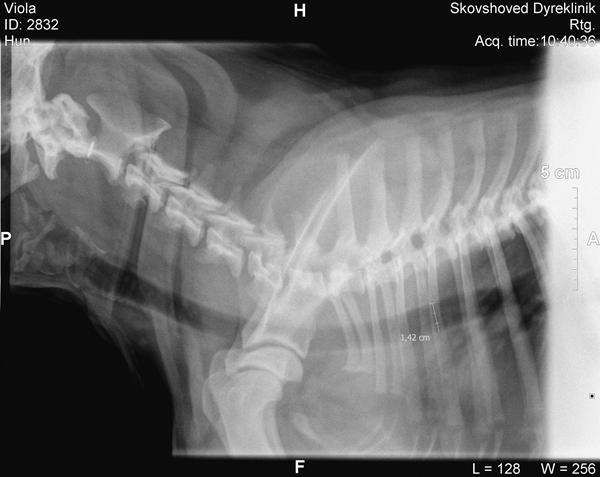

Den ene var ca.1½ år og havde 14,2 mm udfra 3 ribben.